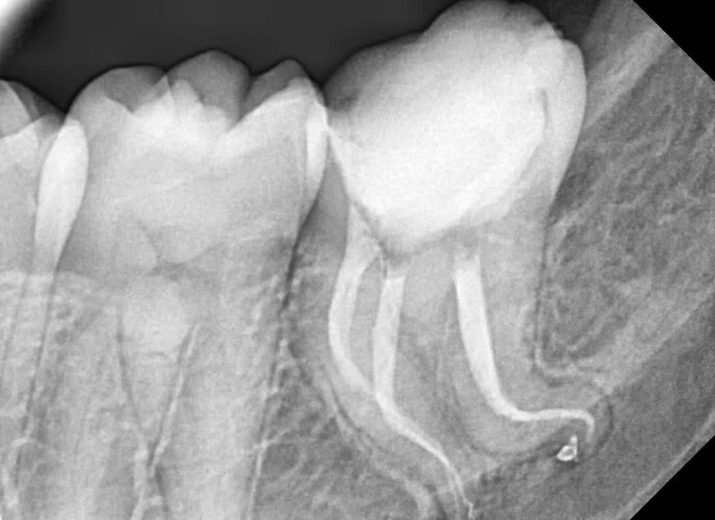

Severe curve:mandibular left second molar